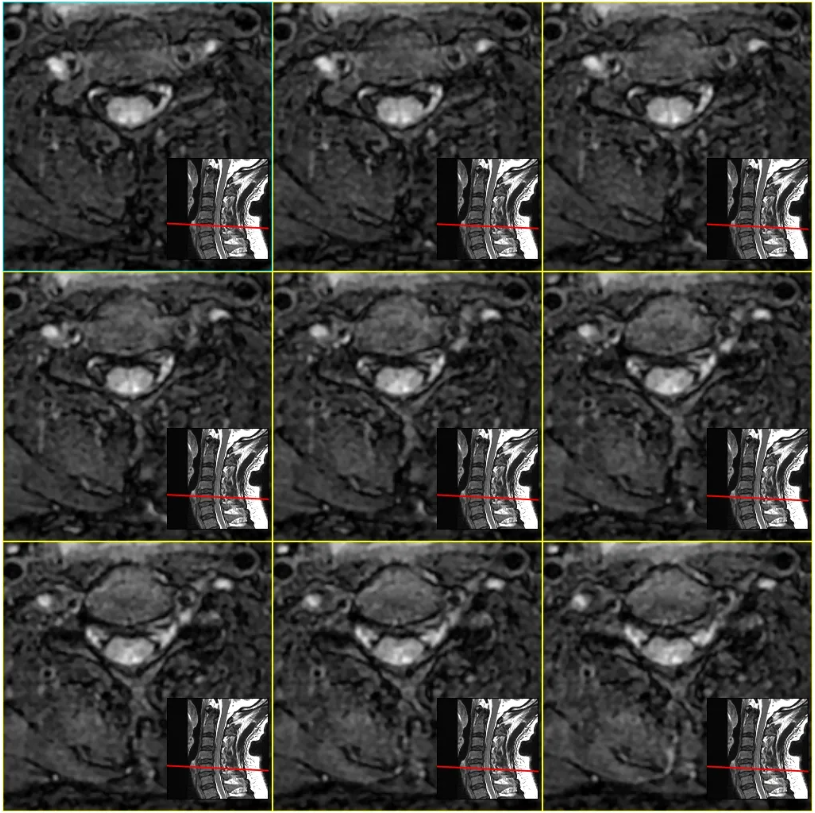

伪影吧。参数有问题。机器好久没有停机保养了。 放病人下来? 赶紧弄下一个, 晚饭约了心仪许久的妹子(帅哥)。。。 三、放患者走,还是继续扫描? 这是一个哲学问题! Ax CUBE T2FLAIR来一个吧。妹子(帅哥)应该不会因为晚到4分钟生气吧。。

重建效果图: